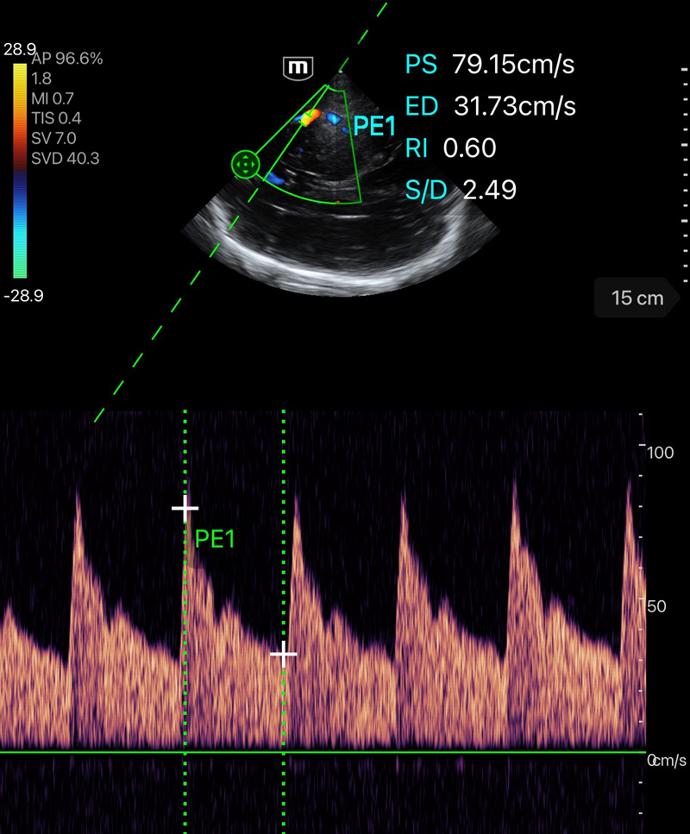

Професионално качество на диагностичните изображения

Различни режими на изображението

Множество режими за сканиране

PW mode

PW Auto Trace

Пулсов доплер с автоматично очертаване на вълната - за измерване на скоростта на кръвния поток.

Клинични снимки